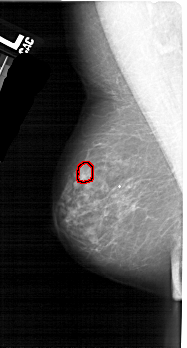

A_1536_1.LEFT_MLO

LEFT_MLO LINES 5206 PIXELS_PER_LINE 2791 BITS_PER_PIXEL 12 RESOLUTION 43.5 OVERLAY

FILE: A_1536_1.LEFT_MLO.OVERLAY

TOTAL_ABNORMALITIES 1

ABNORMALITY 1

LESION_TYPE MASS SHAPE OVAL MARGINS ILL_DEFINED

ASSESSMENT 4

SUBTLETY 3

PATHOLOGY MALIGNANT

TOTAL_OUTLINES 1

BOUNDARY